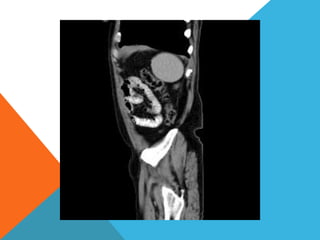

El paciente presentó síntomas de sangrado digestivo y pérdida de peso. Exámenes revelaron gastritis crónica asociada a H. pylori. Un tumor fue descubierto en una colonoscopia normal. La cirugía removió un tumor fibroide solitario, una rara neoplasia mesenquimal que usualmente crece lento y tiene bajo potencial de malignidad. El pronóstico después de la remoción quirúrgica es generalmente bueno.